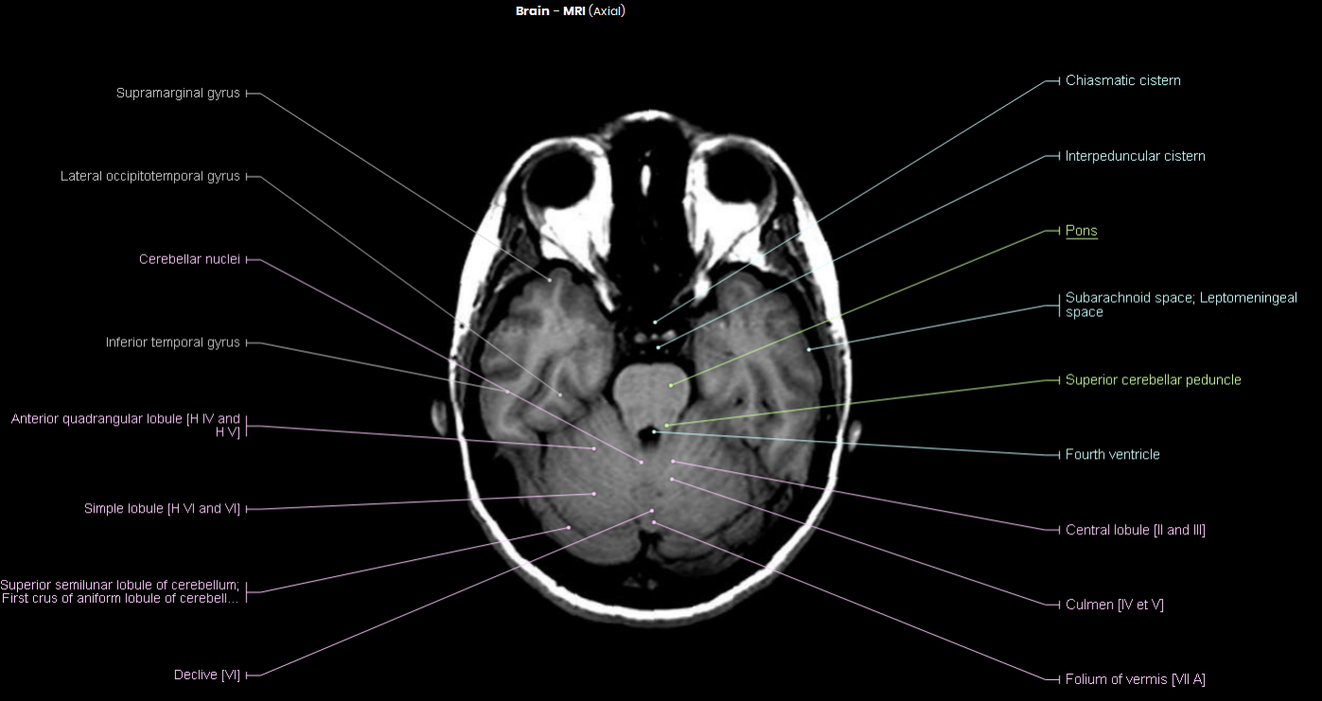

Mri Brain Axial Labelled . information to help patients understand their brain mri radiology report. learn how to read a brain mri using different sequences, such as t1w, t2w, or flair. Learn how to use the interactive interface, abbreviations, and examples of brain sections. Lean about the various sections of report including type. Case contributed by craig hacking. See examples of normal brain anatomy and pathology. learn and explore the axial cross sectional anatomy of the brain with this free tool. a series of labeled imaging anatomy cases by body region and modality, including brain ct head. The case is contributed by. a case study of brain mri with annotations of major structures, such as the frontal, parietal, temporal and occipital lobes. Use the mouse scroll wheel or the arrows to. explore the anatomy of the brain with mri scans and topographic divisions.

Mri Brain Axial Labelled Case contributed by craig hacking. The case is contributed by. Case contributed by craig hacking. a case study of brain mri with annotations of major structures, such as the frontal, parietal, temporal and occipital lobes. Lean about the various sections of report including type. learn how to read a brain mri using different sequences, such as t1w, t2w, or flair. information to help patients understand their brain mri radiology report. a series of labeled imaging anatomy cases by body region and modality, including brain ct head. Learn how to use the interactive interface, abbreviations, and examples of brain sections. Use the mouse scroll wheel or the arrows to. See examples of normal brain anatomy and pathology. explore the anatomy of the brain with mri scans and topographic divisions. learn and explore the axial cross sectional anatomy of the brain with this free tool.

MRI Atlas Brain (Axial) Scan 2 Labeled (Enlarged) Eccles Health Sciences Library J Mri Brain Axial Labelled a series of labeled imaging anatomy cases by body region and modality, including brain ct head. explore the anatomy of the brain with mri scans and topographic divisions. learn and explore the axial cross sectional anatomy of the brain with this free tool. See examples of normal brain anatomy and pathology. information to help patients understand. Mri Brain Axial Labelled.